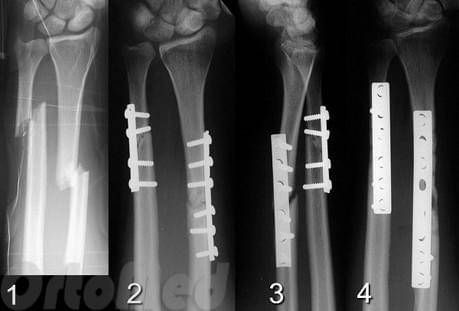

Для стабильно-функционального остеосинтеза костей предплечья применяют пластины (узкие, желобоватые, реконструктивные и малые Т-образные), малые спонгиозные, кортикальные винты, а также 8-образный серкляж.

Остеосинтез стержнями часто не обеспечивает стабильной фиксации, а введение прямого стержня в лучевую кость приводит к выравниванию физиологической кривизны лучевой кости, что ведет к нарушению ротационных движений.

При переломах локтевого отростка прочная фиксация достигается при применении метода 8-образного серкляжа, при оскольчатых переломах в ряде случаев целесообразна дополнительная фиксация малым спонгиозным винтом.

Остеосинтез локтевого отростка методом 8-образного серкляжа.

При переломе венечного отростка остеосинтез выполняют 3,5 мм винтом. Для остеосинтеза перелома головки лучевой кости применяют фиксацию малым спонгиозным винтом.

Остеосинтез головки лучевой кости и венечного отростка локтевой винтами.

При переломах диафиза и метафиза обеих костей или изолированных переломах лучевой и локтевой костей остеосинтез производят прямыми узкими, желобоватыми пластинами.

Принципы экстракортикального остеосинтеза костей предплечья.

Остеосинтез при переломах дистального отдела лучевой кости производят редко, как правило, при неудаче консервативного лечения. Для остеосинтеза применяют малую Т-образную пластину (Рис. 140).

Первый винт вводят через продолговатое отверстие в проксимальный отломок, тем самым создавая опору для дистального фрагмента. Сам отломок фиксируют компрессионным спонгиозным винтом через отверстие пластины. Рану ушивают с тщательным восстановлением квадратного пронатора. Движения в лучезапястном суставе разрешают через 3–5 дней.

В некоторых случаях остеосинтез производят спицами или спонгиозным винтом.

Остеосинтез лучевой кости в дистальном отделе

Аппарат внешней фиксации применяют при открытых переломах костей предплечья, а также при переломах дистального отдела предплечья.

При диафизарных переломах предплечья внешний фиксатор применяют как временное устройство до заживления раны мягких тканей, после чего производят внутренний остеосинтез. При закрытом остеосинтезе в исключительных случаях для анатомической репозиции можно выполнить малый разрез над линией перелома.

Вешняя фиксация при переломе лучевой кости в типичном месте.

После стабильно-функционального остеосинтеза костей предплечья обычно иммобилизация в гипсовой повязке не требуется. С первых дней после остеосинтеза назначается лечебная гимнастика направленная на восстановление функции травмированной конечности.